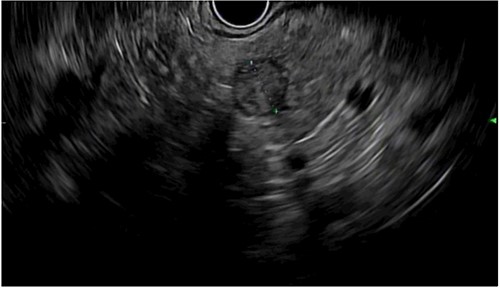

The patient is a 29-year-old female with a history of MEN1, stage II (pT3N0) pancreatic tail neuroendocrine tumor, hyperparathyroidism and recurrent episodes of kidney stones. She underwent a robotic-assisted distal splenopancreatectomy and, after 18 months of follow-up, a magnetic resonance imaging showed a 1 cm lesion in the pancreatic body (Fig. 1A and B). An endoscopic ultrasound reported a 13 × 10 mm solid lesion (Fig. 2). A biopsy was taken, and the histopathology informed a neuroendocrine tumor recurrence.

Endoscopic ultrasound showing a 13 × 10 mm solid lesion in the pancreatic remnant.